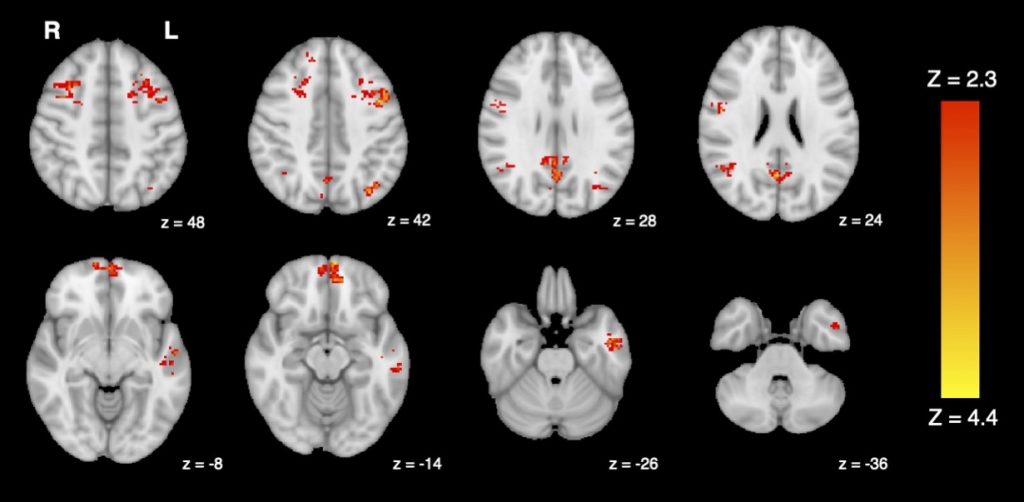

В ходе эксперимента ученые тестировали воздействие выхлопных газов дизельного двигателя и фильтрованного воздуха на 25 здоровых взрослых людях. Активность мозга исследователи измеряли с помощью функциональной магнитно-резонансной томографии (фМРТ).

Фото: Jodie R. Gawryluk et al., Environmental Health, University of British Columbia

Исследование показало уменьшение функциональной связности, то есть, насколько хорошо различные области мозга коммуницируют друг с другом после воздействия выхлопных газов дизельного двигателя.